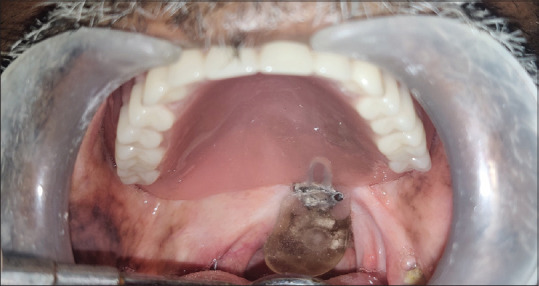

A male patient aged 60 years reported to the Department of Prosthodontics, Tamil Nadu Government Dental College and Hospital, with a chief complaint of hypernasality with speech, nasal regurgitation, and complete edentulism. The patient had a history of squamous cell carcinoma of the oropharynx, involving the left side of the soft palate. Surgical excision was done 4 years back, followed by concurrent chemoradiotherapy. The size of the defect was 2 cm × 3 cm with slight deviation of uvula to the left side [Figure 1].

Figure 1.

Intraoral view of defect involving left side of soft palate with deviation of the uvula to the respective side